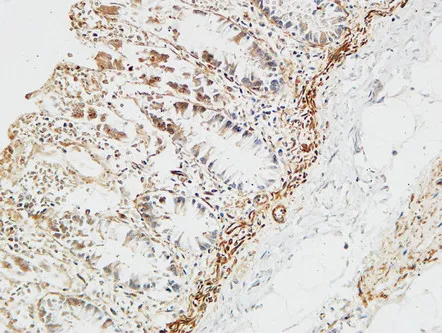

Cytokeratin 8 (phospho Ser73) Rabbit Polyclonal Antibody

Cat: APRab04533

Size1:50μl Price1:$128

Size2:100μl Price2:$230

Size3:500μl Price3:$980